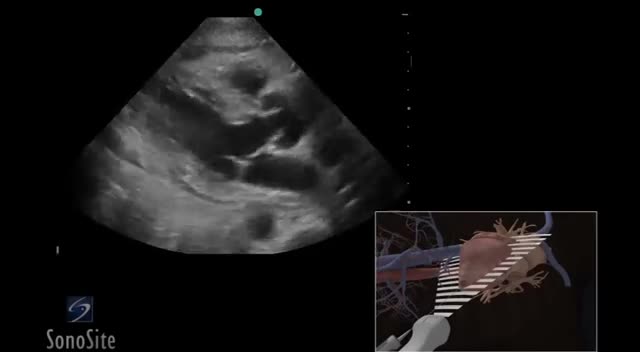

3D How To: Ultrasound Guided Paricardiocentesis Procedure - SonoSite Ultrasound

3D How To: Ultrasound Guided Paricardiocentesis Procedure - SonoSite Ultrasound samer kareem 2,106 Views • 2 years ago

Using 3D animations we have come up with a new way of demonstrating how to perform portable ultrasound examinations